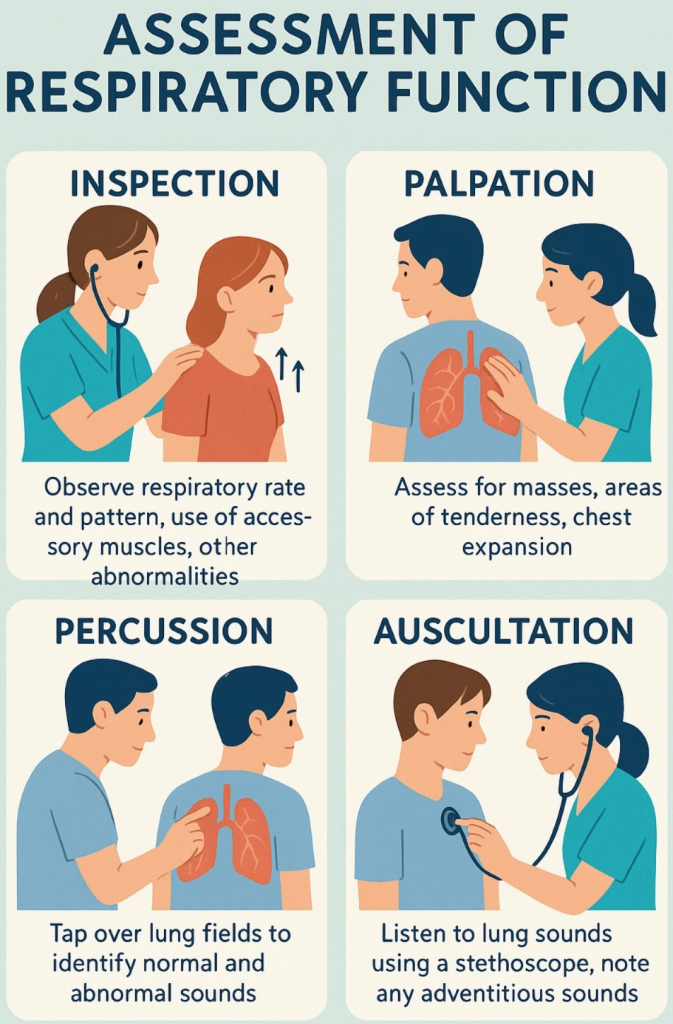

- રેસપાયરેટરી એક્ઝામિનેશનમાં ઇન્સ્પેક્શન, પાલ્પેસન, પરકશન અને અસકલટેશન મેથડનો ઉપયોગ થાય છે.

Palpation (પાલપેશન):

- થોરાસિક પાલપેશનમાં થોરાસિક એરિયાને પાલપેટ કરવામાં આવે છે.

- જેમાં ચેસ્ટના ફ્રન્ટ અને બેકના ભાગને ટેન્ડરનેસ, ડિફોરમિટી અને એબનોર્મલ મુવમેન્ટ માટે પાલપેટ કરવામાં આવે છે.

- આ ઉપરાંત તે એરિયાને પેઇન, લીઝન, રેસ્પાયરેટરી એક્સપાનસન અને ફ્રેમીટસ માટે પાલપેટ કરવામાં આવે છે.

Percussion (પરકશન):

- રેસ્પાયરેટરી પરકશનમાં ચેસ્ટનું ટેપિંગ કરીને અન્ડરલાઇંગ સ્ટ્રકચરને અસેસ કરવામાં આવે છે જેથી ત્યાં એર, ફ્લુઇડ અથવા સોલીડ પ્રેઝન્ટ છે કે નહિ ચેક કરી શકાય.

- જેમાં એન્ટેરીઅર અને પોસ્ટેરીઅર ચેસ્ટને સાઇડ ટુ સાઇડ અને ટોપ ટુ બોટ્ટમ ટેપિંગ કરવામાં આવે છે અને તેના દ્વારા સાંભળવાં મળતા સાઉન્ડને નોટ કરવામાં આવે છે.

Auscultation (અસ્કલટેશન):

- અસ્કલટેશનમાં સ્ટેથોસ્કોપની મદદથી લંગ સાઉન્ડ સાંભળવામાં આવે છે.

- સ્ટેથોસ્કોપની મદદથી નોર્મલ લંગ સાઉન્ડની કેરેક્ટરિસ્ટિક નોટ કરવી જેમ કે લોકેશન, ક્વોલિટી, ઇન્ટેન્સિટી

- આ ઉપરાંત કોઈપણ પ્રકારના એબનોર્મલ લંગ સાઉન્ડ સાંભળવા મળે છે કે નહીં તે અસ્કલટેટ કરવું.